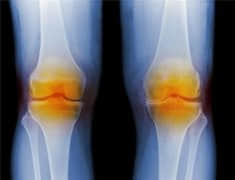

膝关节骨性关节炎的临床表现

跑者如何评估膝盖的磨损程度?